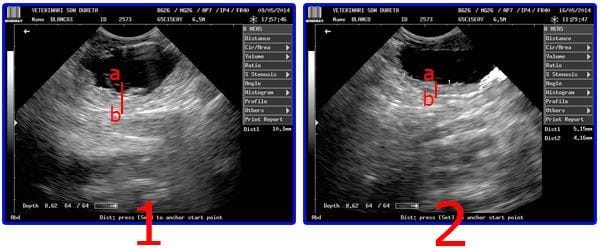

En la ecografía nº 1 se observa la mucosa muy engrosada y arrugada (mas de 10 mm ) con desprendimientos que son los que obstruyen la uretra de Blanco. Uns semana más tarde en la ecografía nº 2 la mucosa es más lisa, sin desprendimientos y con la inflamación reducida a la mitad

Blanco llegó a la Clínica Veterinaria Son Dureta con un cuadro agudo de dolor, con la vejiga completamente inflamada, la uretra colapsada y también con un prolapso rectal producido por el esfuerzo al intentar orinar (El prolapso se produce cuando parte del recto sale al exterior por el esfínter). El primer paso del servicio de urgencias 24 horas de la Clínica Veterinaria Son Dureta fue realizar el diagnóstico por imagen, comprobando que si bien los intestinos estaban en buenas condiciones, la vejiga sufría una gran inflamación. Inmediatamente se pusieron manos a la obra para reducir el prolapso y sondar a “Blanco”, a la espera de los resultados de los análisis. Éstos demostraron que la cistitis que padecía no se debía a ninguna infección y tampoco aparecieron rastros de sedimento urinario (cristales), con lo que confirmaba estrés como principal causa. El diagnóstico fue cistitis idiopática por estrés y principio de lipidosis hepática por falta de alimento.